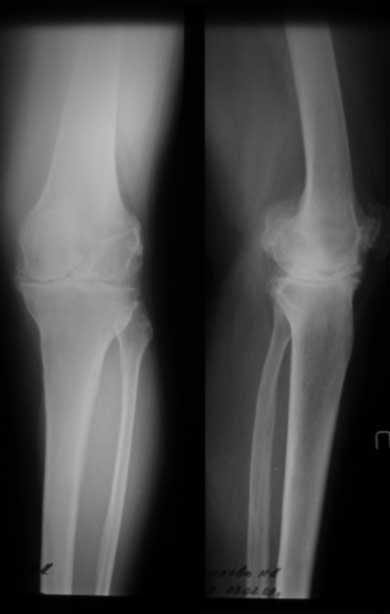

Уважаемые коллеги, как боретесь с ригидным коленом в положении разгибания при эндопротезировании? Пациентка 67 лет, ригидное колено в положении полного разгибания с качательными движениями до 5 град. Прооперировали внутренним доступом с отсечением бугристости. Сгибание до рефиксации бугристости - до острого угла, после максимум с/р 20-25/0/0. Выполнили миолиз доступных отделов 4-х главой мышцы бедра из доступа без особого результата. Основная проблема была в разгибательном аппарате, как с этим боретесь? До эндопротезировыания или после - полноценные операции на разгибательном аппарате как при контрактурах. P.S. снимки выложу чуть позже (не могу добиться нормальных проекций), грубых косяков пока не заметил (увеличенный offset и т.д.) С уважением Максим Агалаков, Е-бург

снимки